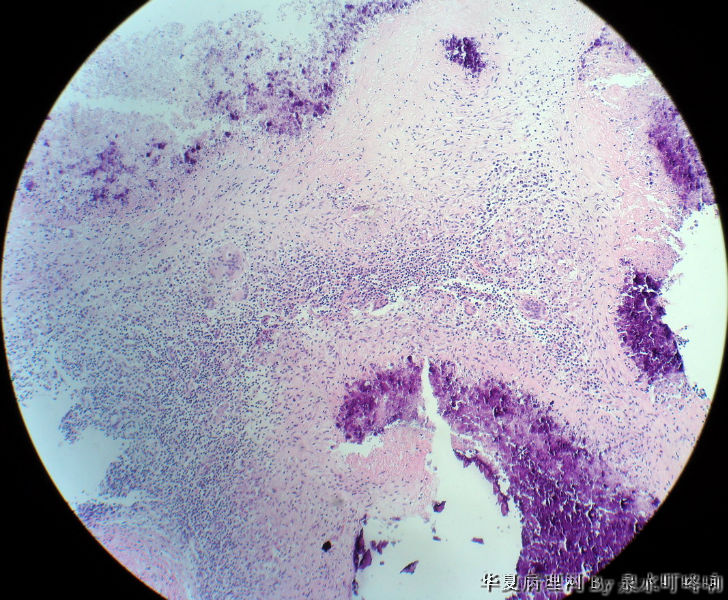

左腋窝肿物

• 左腋窝肿物图3

图3

女,3岁,主因左腋窝肿物半年,术中见为肿大淋巴结,淋巴结内有脓液及坏死组织。

大体:灰红色组织一块,大小约4.6×3.5×2厘米,切面可见两个囊性区域,内容乳白色浓稠液体。

肉芽肿性炎(建议做抗酸染色,除外结核)

是淋巴结吧,淋巴结肉芽肿性炎伴坏死,建议做抗酸染色。

肉芽肿性炎,考虑结核伴钙化。